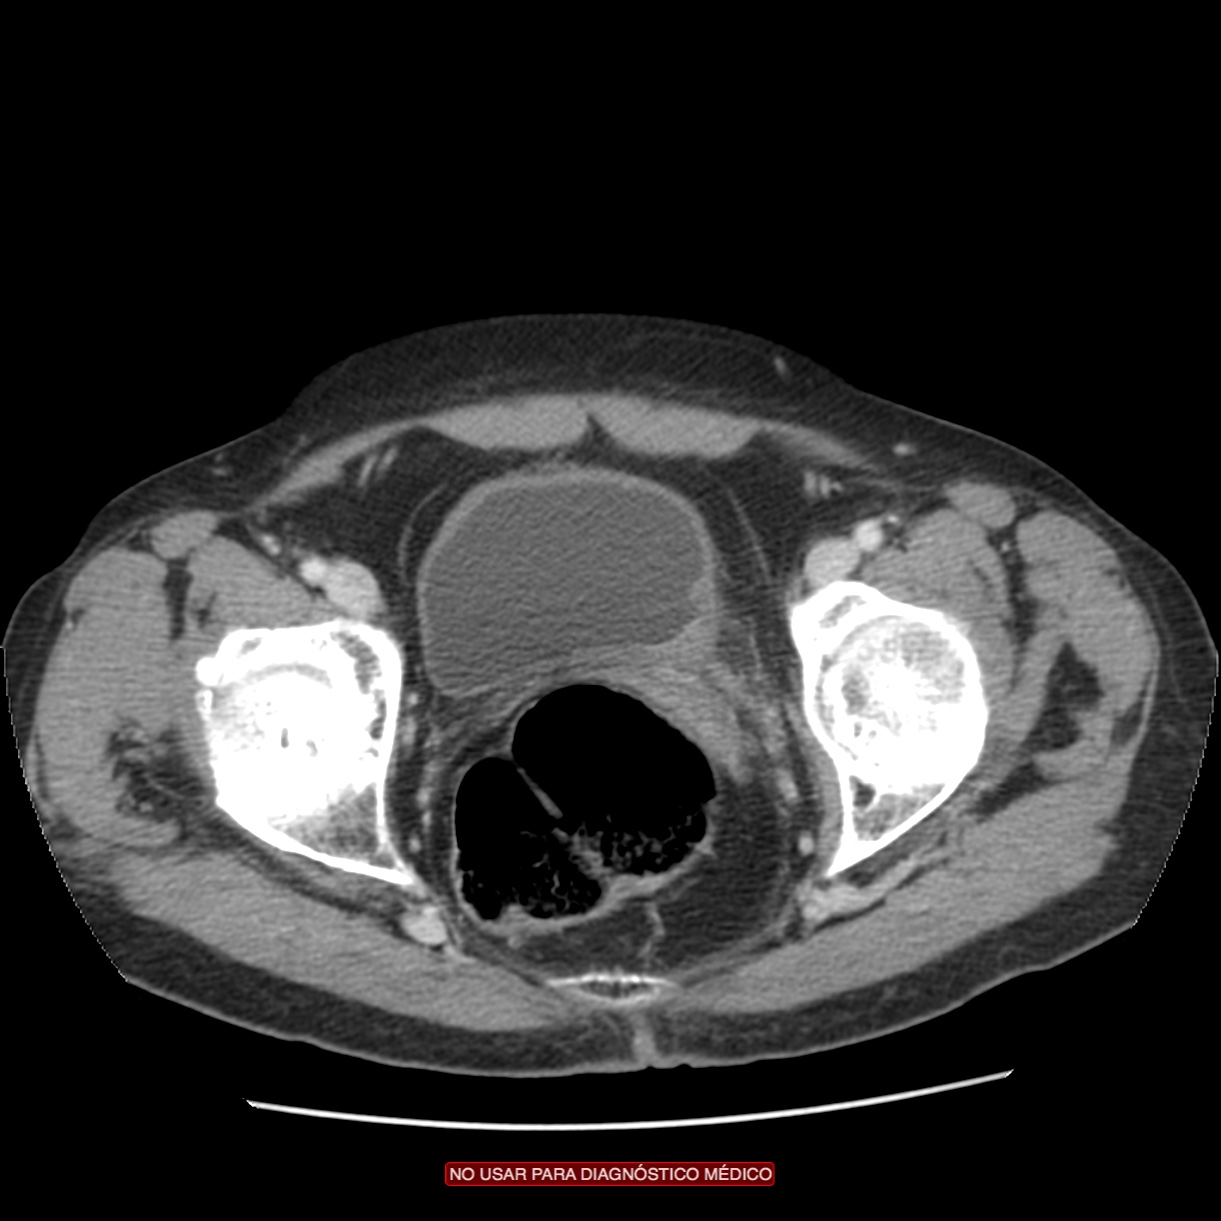

CASO CLÍNICO: Recopilatoción.

Paciente de 59 años con antecedentes personales de Cá de vejiga.

Se le realiza una Uro-Tc por seguimiento al año, aunque en esta ocasión el paciente refiere episodio de hematuria.

Tras el tratamiento de la recidiva y nefrostomía para la hidroureteronefrosis, vuelve acudir al hospital a los 9 meses por episodio de dolor en FD y malestar general. Se realiza una ecografía de urgencias.

Se realiza nueva TC bifásico abdominopélvio y Uro TC.

- Paciente con numerosas recidivas por Cá vejiga.

- Ha desarrollado un tumor metacrónico en pelvis renal derecha, también responsable de la hidroureteronefrosis.

- Mala evolución radiológica del proceso a expensas de metástasis pulmonares y hepáticas.